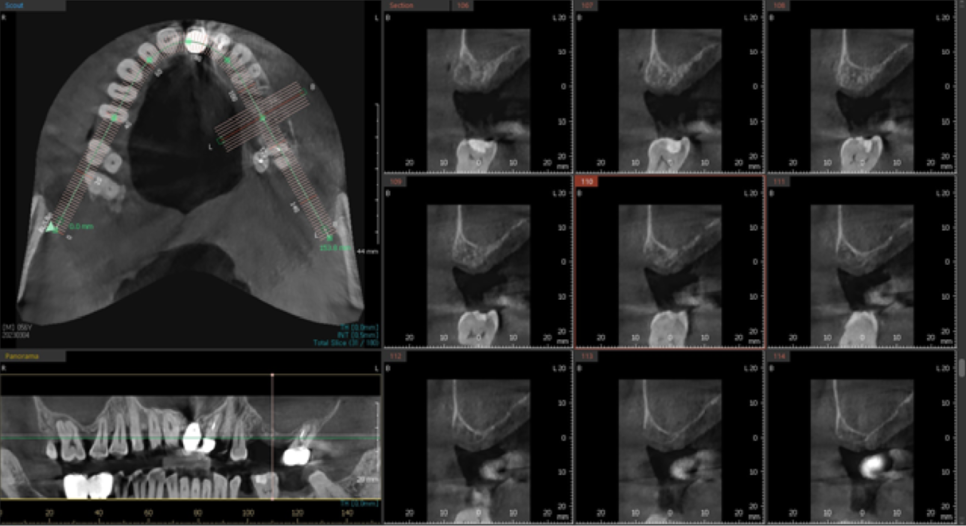

이제 왼쪽 위 작은어금니와 큰어금니 임플란트 식립을 하기로 했습니다.

위에서 잠깐 말씀드린 것처럼,

임플란트를 식립할 뼈의 두께가 얇기 때문에

상악동 거상술을 시행해야 하는데,

3차원 CT상으로 상악동에 염증이 보였습니다.

염증치료를 위해 이비인후과 치료를 병행하였습니다.

이비인후과 치료를 병행 후에,

다시 3차원 CT를 촬영하여 상악동 내에 염증이 줄어든 것을 확인하고

왼쪽 위 임플란트 식립 수술과 상악동거상술을 진행하였습니다.

상악동 거상술도 잘 되고,

뼈이식도 하얗게 잘 된 것을 보실 수 있습니다.

왼쪽 위 상악동거상술과 임플란트 식립수술을 한 지 다섯달정도 지났습니다.

뼈의 두께가 얇아서 상악동거상술을 진행했고, 상악동에 염증이 있는 상태였습니다.

뼈이식을 충분히 했고, 뼈와 임플란트가 잘 유착될 수 있도록 충분히 기다렸습니다.

엑스레이상으로 고정이 잘 되어 보입니다.